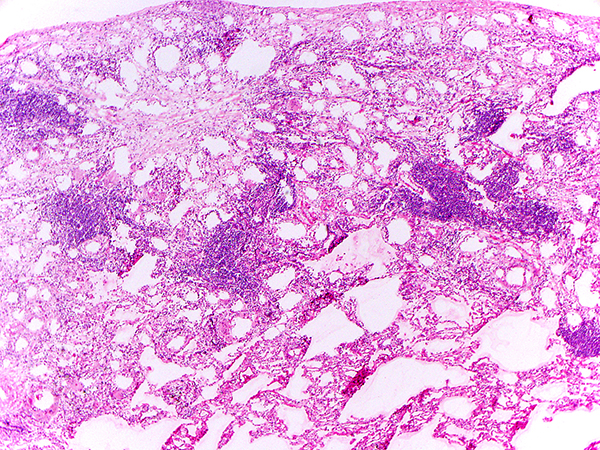

Clinical History:A 85-year-old female former smoker with a history of thyroid and breast cancer presented with a 10-cm right-sided lower lobe pleural-based mass and a separate 2-cm triangular opacity in the dependent aspect of the right middle lobe of lung along the major fissure. CT-guided biopsy of the 10-cm mass demonstrated a solitary fibrous tumor. The patient underwent resection of the right lower lobe mass and wedge resection of the right middle lobe lesion. An intraoperative frozen section of the 2-cm right middle lobe lesion is shown in Figures 1-2.

Q1. During intraoperative consultation, in review of Figures 1-2, which of the following is the appropriate interpretation for this 2-cm lesion:

Given its distinctive morphology, differential diagnosis for exogenous lipoid pneumonia is relatively narrow. Once one recognizes its reactive nature with its characteristic lipid vacuoles, other histiocytic disorders such as Rosai-Dorfman disease and Erdheim-Chester disease can be excluded. Endogenous lipoid pneumonia, in which the accumulated lipid is derived from intrinsic metabolism rather than exogenous source, may be considered, though the cytoplasm of the histiocytes is often more foamy (microvesicular) lacking conspicuous large vacuoles, and it is often associated with bronchial obstruction rather than exogenous lipid use. Of note, during intraoperative consultation for a lung mass/nodule, exogeneous lipoid pneumonia may be confused with granulomatous infection due to the combination of inflammation and giant cell reaction. If vacant holes associated with giant cells are recognized and the possibility of lipid vacuoles are considered, Oil Red O stain (or other lipid stains) would help confirming the diagnosis. While the clinical course of exogenous lipoid pneumonia may be variable, depending on its extent and distribution and the patient’s constitution, once the use of the offending agent ceases, it is generally benign.